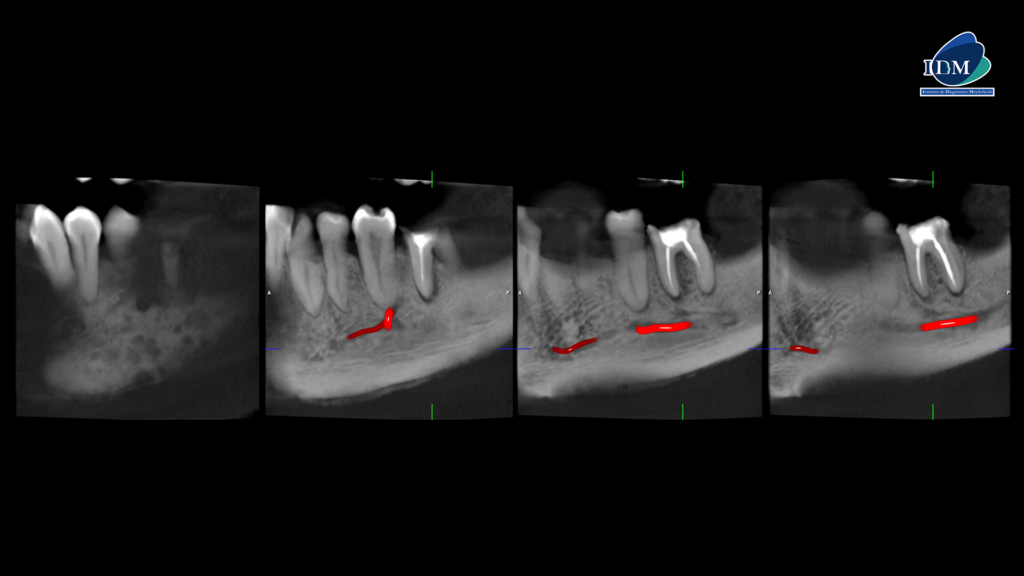

En el estudio complementario mediante tomografía computarizada de haz cónico (TCHC), se confirma la presencia de una reacción ósea perióstica que afecta la tabla ósea vestibular, la basal mandibular y, parcialmente, la tabla ósea lingual en su región caudal (cortes axiales, tangenciales y transaxiales). En las piezas dentarias, se observa una obturación parcial de los conductos y procesos osteolíticos periapicales en la pieza 36 (cortes transaxiales).

Además, se identifica un ensanchamiento del espacio del ligamento periodontal en la región periapical de la pieza 35 (cortes transaxiales).

CORTES TANGENCIALES